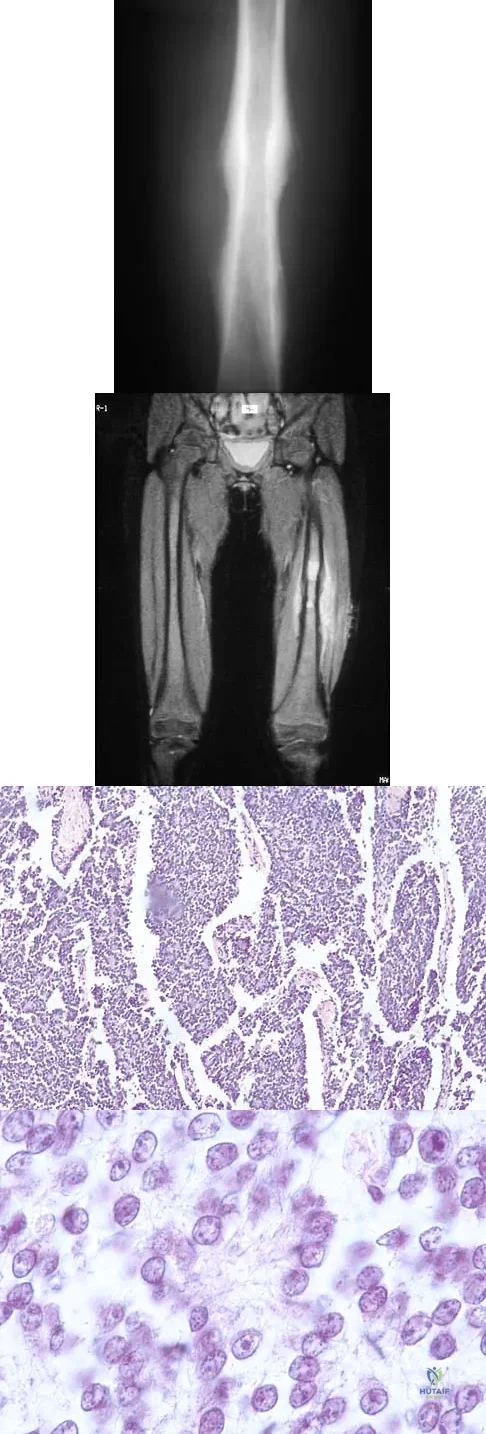

Question 60

A 16-year-old boy has had thigh pain for the past several months. He denies any history of trauma. Examination reveals a large, deeply fixed, soft-tissue mass in the thigh. Laboratory results show an elevated erythrocyte sedimentation rate (ESR) and leukocytosis. A plain radiograph and MRI scan are shown in Figures 1a and 1b. Biopsy specimens are shown in Figures 1c and 1d. What is the most likely diagnosis?

Explanation